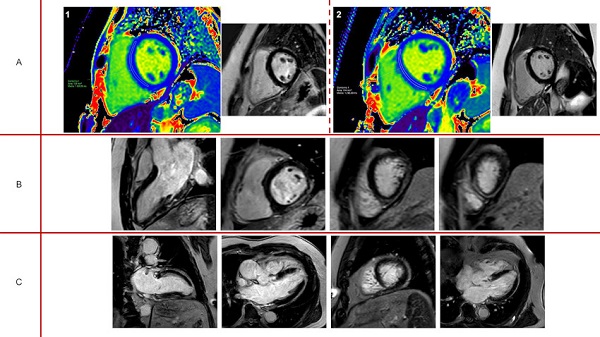

Panel A: 1. paciente con señal de T1-mapping aumentada (1310 mseg), sin signos de fibrosis focal; 2. mismo paciente en estudio de seguimiento a los 5 meses con señal de T1-mapping normal (1246 mseg). Panel B: Realce tardío subepicárdico inferolateral e inferior en paciente con diagnóstico de miocarditis. Panel C: Realce tardío subendocárdico inferoapical y apical estricto, compatible con secuela de etiología isquémica.

Por otro lado, 31 pacientes (10,4%) presentaron alteraciones exclusivamente en los mapas paramétricos (T1-mapping en 29 casos, T1- y T2- mapping en 2 casos), sin otros criterios que sostuvieran el diagnóstico de miocarditis (clínica, cambios en el ECG, fibrosis miocárdica subepicárdica, etc). A este grupo se los interpretó como portadores de cambios inflamatorios aislados (grupo C). Entre estos pacientes, 6 fueron sometidos a una segunda RMC, con una media de 159 días de diferencia (rango 105-189 días). En todos los casos se observó la normalización de la señal de T1mapping. (Figura 3)

En 31 casos se observó una señal de T1-mapping elevada, sin otros signos de fibrosis miocárdica significativa (6 de estos casos presentaban RTG lineal intramiocárdico en septum basal, considerado inespecífico). En estos casos, en el informe se sugirió el seguimiento evolutivo y eventualmente repetir el estudio sin contraste endovenoso a los 4-6 meses. Seis pacientes se realizaron RMC en el seguimiento y en todos los casos la señal de T1-mapping disminuyó a valores dentro del rango normal, lo que interpretamos como la resolución de un proceso inflamatorio que no dejó secuelas. Excluyendo el sexo, no identificamos variables clínicas predictoras de T1-mapping elevado (se estudiaron edad, síntomas al inicio, requerimiento de internación, presencia de síntomas persistentes, días desde el alta al estudio, hallazgos de laboratorio, entre otras) (Figura 5).